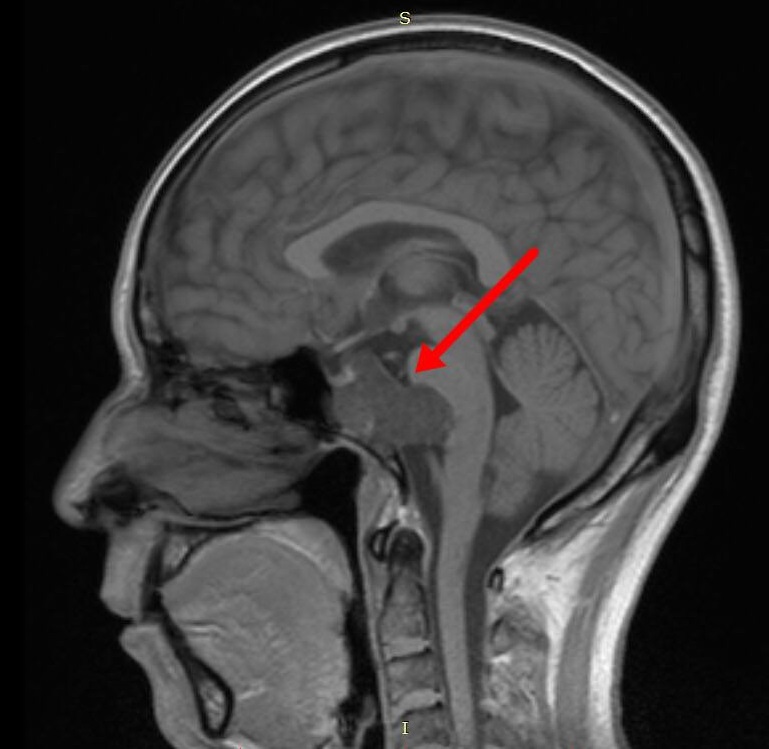

颅底脊索瘤(五):影像特点

头痛医头一一之颅内脊索瘤